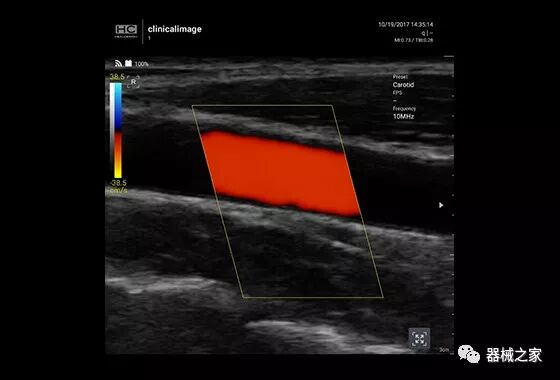

在几年前,超声波无法对小型慢流血管中的血流进行成像,但现在有少数供应商提供具有此功能的系统。该特征提供了另外一种检查病变以指示癌症或炎症的方法。其中一个是佳能Aplio 900 CV系统,它可以显示毛细血管中的血流量。日立的Arietta 65中程系统提供了一种可视化小血管的功能,可以更好地观察肾脏等器官的灌注情况。三星RS85还提供MV-Flow可视化慢流微血管结构。